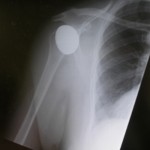

Total Shoulder Replacement